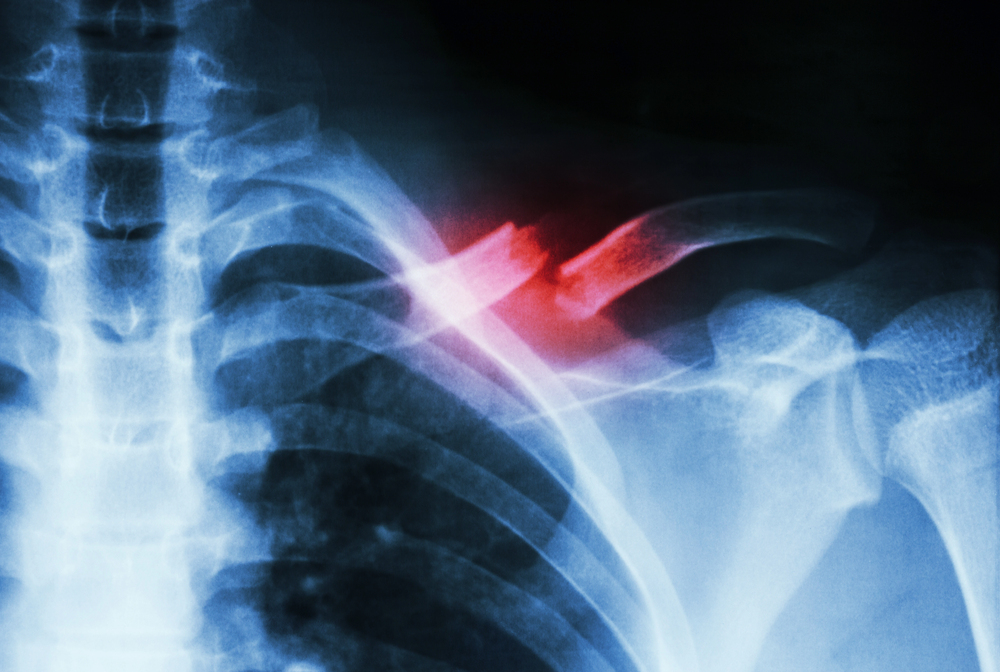

Types of Fractures in Nursing Homes and Assisted Living Facilities

Bone fractures in elderly patients can vary significantly, depending on the location, cause, and severity of the injury.

Traumatic fractures result from significant external force or trauma, such as falls, collisions, or physical abuse within care facilities. These fractures frequently affect the hips, pelvis, wrists, arms, and femur. A traumatic fracture can indicate serious underlying issues like lack of proper supervision, failure to implement fall prevention measures, or unsafe environmental conditions.